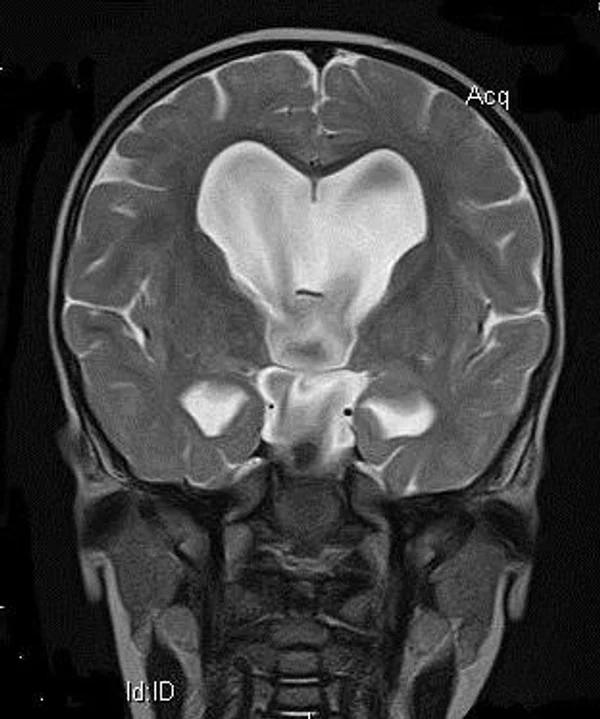

кисты, аномалии Денди-Уокера и др.Операции при внутричерепных кистах. В основном встречаются арахноидальные кисты различных локализаций и кисты сосудистых сплетений боковых желудочков. Пациентам с врождёнными кистами операции проводятся в следующих ситуациях: увеличении объема кисты в динамике, наличии клинических проявлений, компрессии и дислокации мозговых структур, наличии окклюзии ликворных путей. Нами используются 2 способа хирургического лечения кист: эндоскопическая перфорация стенок кист и открытая резекция кист. Открытая резекция кист проводится при ретроцеребеллярных арахноидальных кистах (рис. 2), при арахноидальных кистах межполушарной щели при отсутствии непосредственного контакта их стенок со стенками расширенных желудочков головного мозга и повторного увеличения кист средней черепной ямки после эндоскопической кисто-цистерностомии. Техника операции заключается в проведение краниотомии и максимальном иссечении стенок кист с созданием широкого сообщения кист с субарахноидальным пространством. Эндоскопические операции проводятся при арахноидальных кистах межножковой и пинеальной цистерн, арахноидальных кистах межполушарной щели при тесном контакте их стенок со стенками расширенной желудочковой системы (рис. 3), первично при арахноидальных кистах средней черепной ямки, а также при кистах сосудистых сплетений боковых желудочков. При арахноидальных кистах межножковой цистерны эндоскопически проводится перфорация стенок кисты, сообщая ее с просветом III желудочка и межножковой цистерной – эндоскопическая вентрикуло-кисто-цистерностомия (рис. 4). При арахноидальных кистах пинеальной цистерны проводится перфорация кисты в передне-верхних её отделах с созданием сообщения полости кисты с просветом III желудочка – эндоскопическая кисто-вентрикулостомия. С целью предотвращения облитерации сформированного отверстия иногда в полость кисты под контролем эндоскопа вводится стент перфорированный на протяжении (рис. 5, 6). Эндоскопическая кисто-цистерностомия выполняется при арахноидальных кистах средней черепной ямки. При этом создается широкое сообщение кисты с базальными цистернами. При кистах сосудистых сплетений боковых желудочков проводится их вскрытие в просвет боковых желудочков – эндоскопическая кисто-вентрикулостомия. При множественных кистах проводится их хирургическое сообщение между собой – интеркистосмия